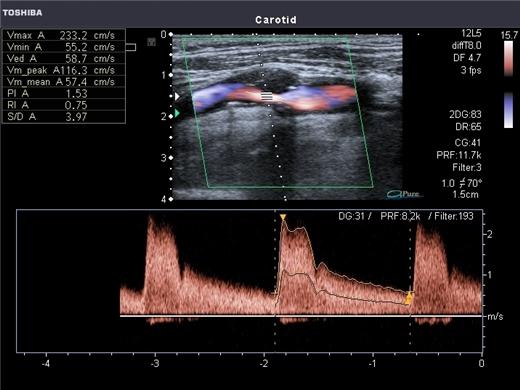

Ультразвуковое дуплексное сканирование вен нижних конечностей Киев является современным и неинвазивным методом, с помощью которого происходит воспроизведение сосудистой системы на мониторе в двухмерном изображении и проводиться оценка состояния сосудистых стенок, характер и скорость тока крови по сосудам. Во время исследования специалист на мониторе специального компьютера видит патологические изменения в строении сосудов, места сужения просвета сосуда, различные расширения или закупорки просвета. Также специалист выявляет нарушения кровотока, тромбы, атеросклеротические бляшки, застойные процессы и нарушения клапанной системы. Специалисты рекомендуют проходить ультразвуковое дуплексное сканирование вен нижних конечностей с целью профилактики один раз в год после 40 лет. Что позволяет избежать развития сложных форм заболевания и выявить патологический процесс на доклинической стадии. Более ответственно к своему здоровью и к состоянию сосудов стоит относиться женщинам. Приблизительно 40% женщин сталкиваются с сосудистыми заболевания ног или другими сосудистыми патологиями.

При дуплексном сканировании сосудов нижних конечностей применяются звуковые волны высокой частоты. Такие волны не воспринимаются человеческим ухом, но обладают специфическими физическими свойствами. Ультразвуковые волны проходят через кожный покров и отбиваются от более плотных тканей. Отражаясь от тканей, такие волны улавливаются специальным датчиком. Компьютер, получив информацию от датчика, передает ее на монитор в виде двухмерного динамического изображения. Современные аппараты для ультразвукового дуплексного сканирования вен нижних конечностей имеют множество преимуществ над ранними аппаратами. Современные аппараты могут измерять скорость, направление кровотока и оценивать структурные изменения стенок сосуда и просвета сосуда (ранее полная оценка сосуда была невозможной). Ультразвуковая диагностика не имеет негативного влияния на организм и может проводиться многократно короткий промежуток времени без вреда для здоровья. Проводят ультразвуковое дуплексное сканирование как пожилым людям, таки маленьким детям.